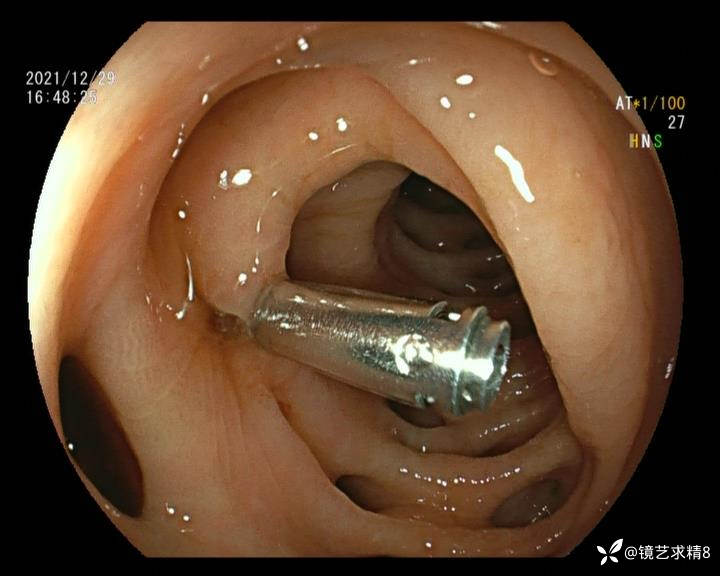

患者以消化道出血入院,胃镜未见异常,肠镜进入乙状结肠就看到很多憩室,同时还看到肠腔用清肠药后移动下来1枚尖锐的枣核,这么多憩室,这个枣核扎入憩室的机会非常大,推测应该是掉入一坑🕳就算出来还会有很多坑🕳🕳🕳等着,掉入憩室内很容易刺破血管,这可能就是消化道出血的原因,继续前进可以看到有一些憩室内翻,还有一些息肉,问题来了,那么多憩室,犯罪分子是抓住了,它在那些憩室内作过案?到达回盲部后挨个冲洗,但憩室大小又不足以把镜头进入憩室内观察,针对有血块的憩室冲洗后可疑出血的以夹子闭合或套扎,取出枣核,如果有锥形透明帽可能钻入憩室精准电凝效果更好,若内镜下操作失败介入治疗成功率更高,经内镜下治疗后观察未再出血出院。